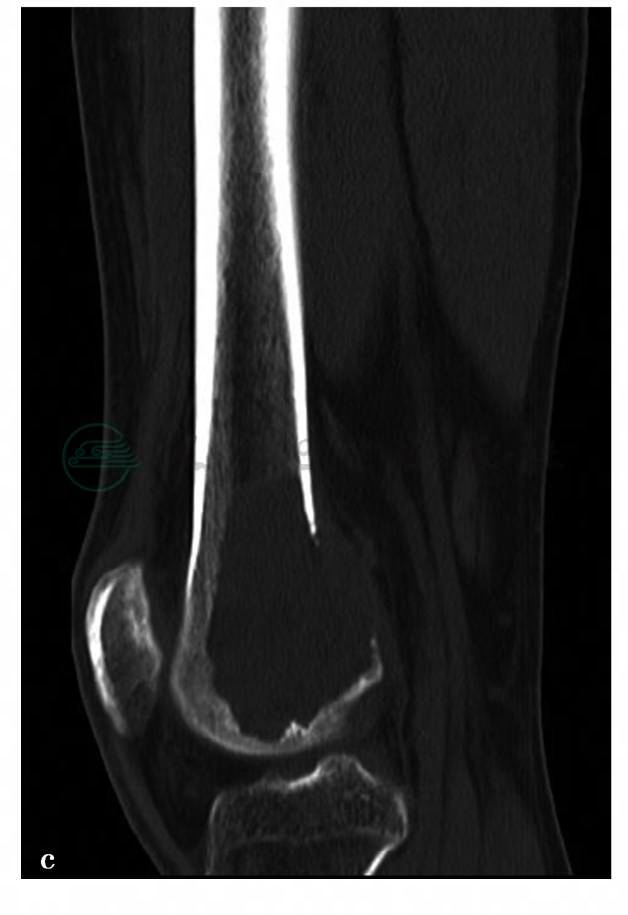

(2)病例2:

X线、CT平扫。

图2 图2a,X线示右股骨远端可见偏向股骨外侧髁的偏心性骨质破坏,病灶大小约6cm×6.5cm,边缘较清楚,无硬化边。病灶位于股骨远端,越过骨骺线,离关节面最近处约0.8cm。受累骨皮质完整,无骨膜反应。周围软组织清晰,无异常表现。图2b、c,CT示右股骨远端偏心性骨质破坏,病灶大小约6cm×6.5cm,略成膨胀性改变,边缘较清无硬化边,密度较均匀,CT值约35HU。后外侧骨皮质部分缺损,病灶内组织通过破损的皮质向后侧突出。无骨膜反应